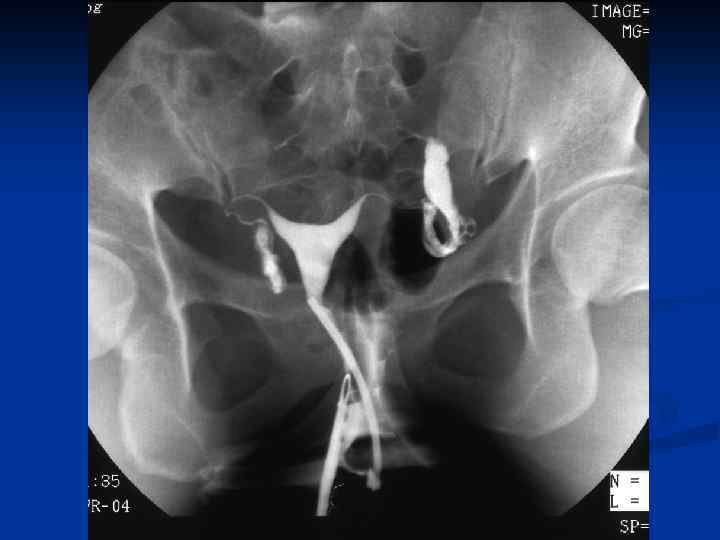

n n n Провести рентгеновское исследование грудной клетки, а если есть показания, то и других органов; Определить туберкулиновую чувствительность; Назначить и провести гистеросальпингографию с 60% раствором водорастворимого верографина, при этом возможно: n n n Определить состояние маточных труб (тонкие, ригидные, запаянные ампулярные отделы, деформация в виде четок, курительных трубок); Выявить форму полости матки, ее размеры, наличие или отсутствие сокращений; Диагностировать наличие / отсутствие рефлюкса контрастного вещества из труб.